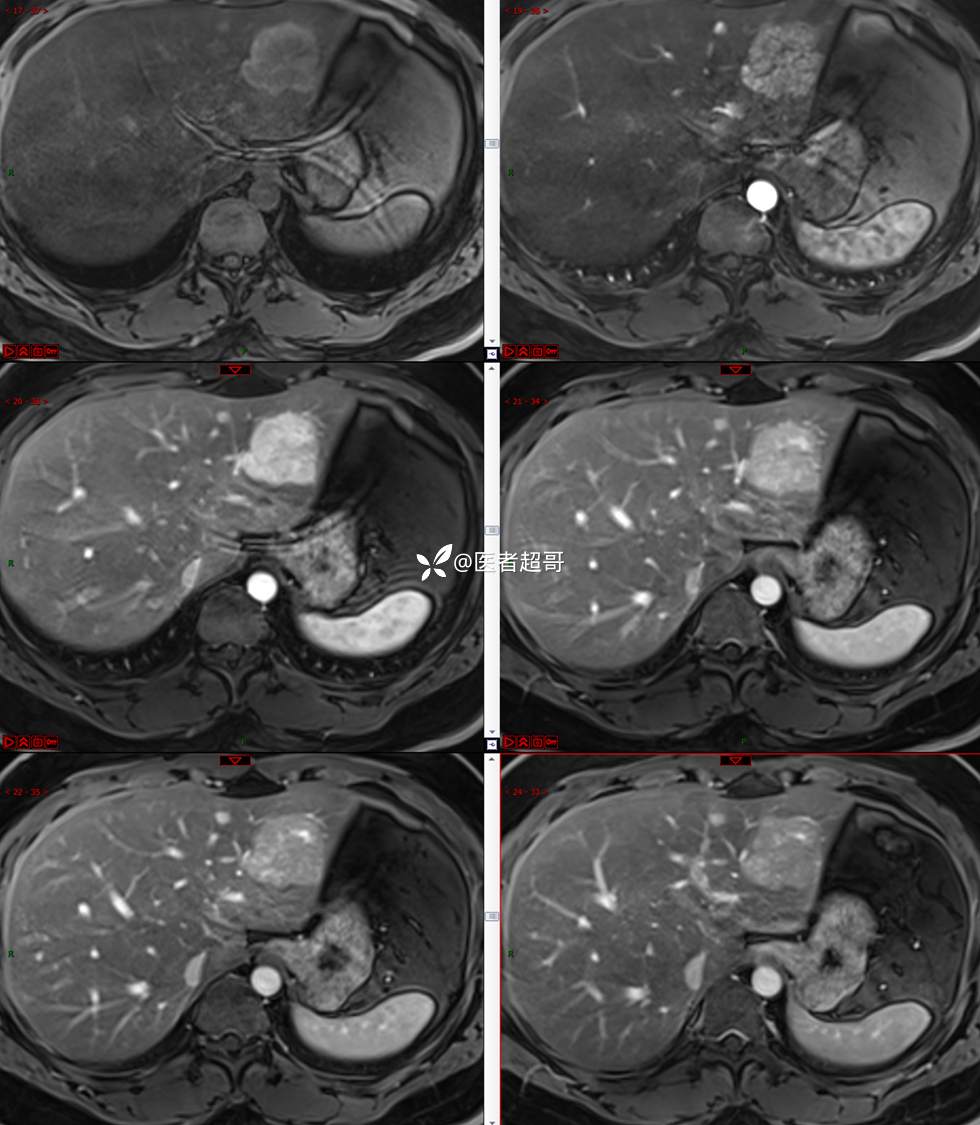

【影诊笔记800】青年男性,肝脏占位,特殊对比剂提示富血供,您能想到啥?有结果!

现病史:患者缘于5天前体检时发现肝占位性病变,未予以特殊处置。现患者为求系统诊治就诊于我院,行普美显提示:肝左叶富血供占位,请结合临床及其他检查,肝多发血管瘤,脂肪肝,肝囊肿,请结合临床。门诊以“肝占位性病变”收入我科。病程中,饮食睡眠可,二便可,近期体重未见明显变化。